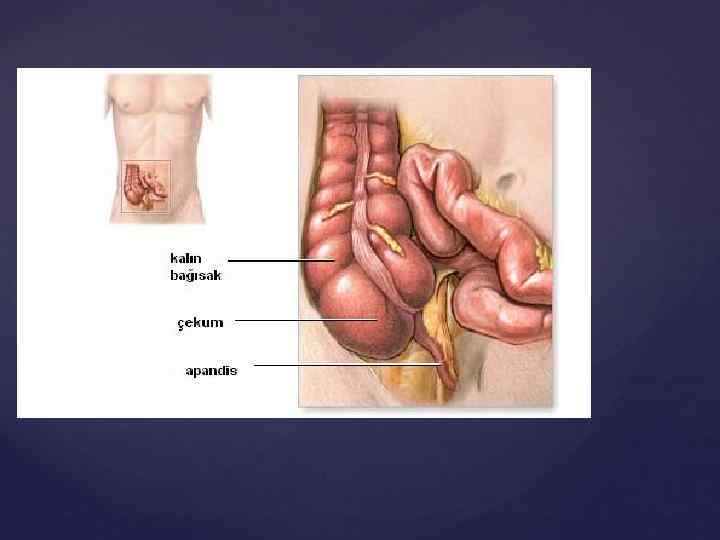

. Іштің жедел басталатын хирургиялық аурулар арасында ішек түйілуі аппендициттен соң екінші болып жиі кездеседі. Ішектер жабысқақтануы - ішек түйілуінің барлық түрлерінің 43 -76% -дейінгі себебі болады, ал мұндай аурулардың 11 -17% өлімге ұшырайды. Ішек өтімсіздігінің патогенезі (су-электролит алмасуының бұзылыстары, жалпы интоксикация және т. б. ), клиникалық көрінісі бірдей. Осыған орай диагностикалық және емдік шара бірдей болады. Жедел ішек өтімсіздігі барлық жастағы адамдарда кездесуі мүмкін. Ең жиі жабысқақты (спаечная) ішек өтімсіздігі кездеседі.

Илеустың жедел, созылмалы және ауыспалы түрлерін бөледі. Жедел илеус - ойда жоқта, бұған дейін дені сау адамда басталып, оның жағдайы тез ауырлайды. Созылмалы илеусқа бәсендеп өсетін ішек ісігі, ал ауыспалы түріне ішектің бұралуы үшыратады. Ішектің толық бітелуі немесе жартылай бітелуі мүмкін. Жартылай бітелуінде нәжіс және газ аздап шығады. Ішек түйілуінің барлық түрлерін механикалық және динамикалық деп екі топқа бөледі. Механикалық деп ішектің бұралуында, қысылуында, бітелуінде, сырттан басылуында байқалатын түрін атайды. Механикалық илеус - странгуляциялық және обтурациялық болып екіге бөлінеді. Странгуляциялық түрінде ішек сыртқы себептен түйіледі. Бұңда ішек ғана емес, оның шажырқайы қысылып қан айналысы бүзылады да қысылған ішектің некрозы басталады.

Странгуляцияға ішек бұралуы, байлануы, қысылуы, күрмелуі себеп болады. Обтурациялық түрінде ішек ісікпен, аскаридамен, дәкелі құрғатқыш (операцияда ұмытылған) бітеледі. Қан айналысы онша бұзылмайды. Өйткені шажырқай қысылмайды. Ішек түйілуінің келесі себебі инвагинация - ішекке ішек еніп оның бітелуіне қоса шажырқайдың қысылып, қан айналысы бұзылуы байқалатындығынан илеустің бұл түрінде обтурация және странгуляция қоса байқалады. Ішектің қабырғасының тегіс етінің әлсізденуіне байланысты кездесетін ішек түйілуі динамикалық деп аталады. Илеустің бұл түрін тырысқан және салды деп екіге бөледі. Спастикалық түрі - ішек қабырғасының тырысуынан оның өзегі тарылуымен байланысты болса, паралитикалық илеусте ішек созылған, өзегі кеңіген, оның тонусы - қозғалуы нашарланған.

Ішек бітелуінің себептері - көп және әр түрлі. Нәрестелерде -ауытқулар және атрезия, ішектің бөгде затпен бітелуі. Ересектерде - ойық жараның тыртықтануы, ішектің қатерлі ісігі немесе басқа мүшенің ісігімен ішектің қысылуы. Қартайғандарда - копростаз, нәжіс тастары, трихобезоар, өт тасы "іште ұмытылып қалған" – дәке, аспап. Ішектің құрттармен бітелуі балаларда жиі кездеседі. Ішек туберкулезінен, дизентериядан, іш сүзегінен соңғы ойық жаралардың тыртықтанып жазылуынан соңғы тарылыстар. Көлденең тоқ ішектің төмендеуі салдарынан ішектің бүгіліп өзегі тарылуы.